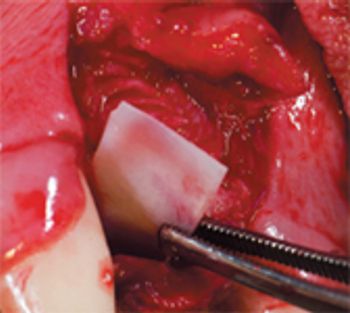

Follow this straightforward, step-by-step guide to remove this large-rooted tooth by creating a mucoperiosteal flap.